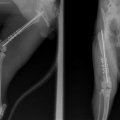

kiisu pareneb. Tal oli puusaluu murd (unustasin pildid lisada siia albumisse, kohe teen).

Praegu taastub ilusti operatsioonist. Keegi ei otsinud teda veel :(